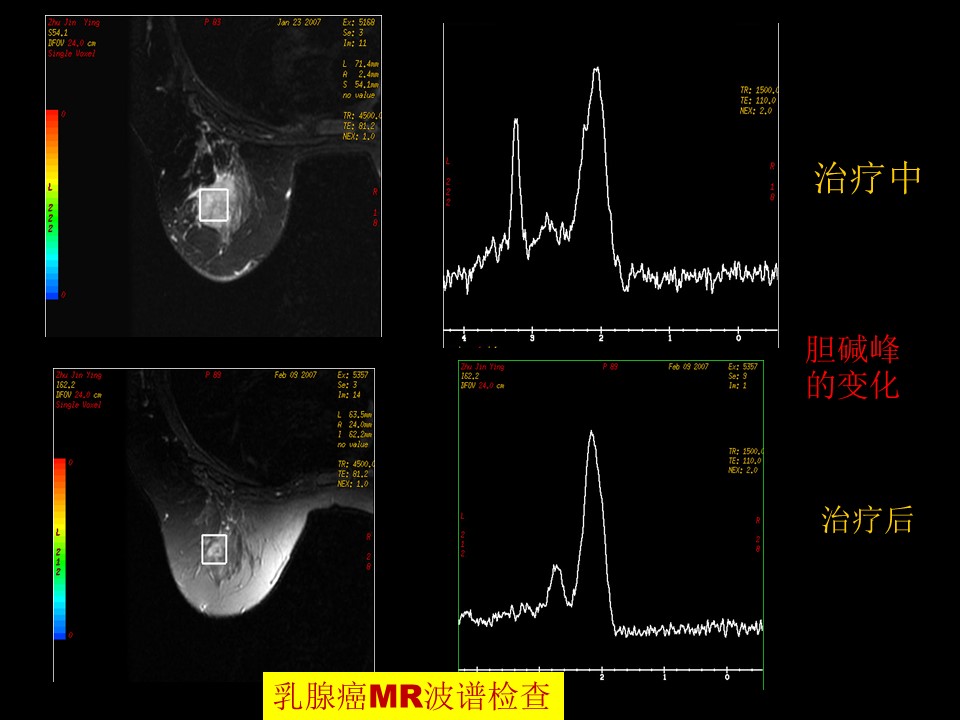

“乳腺癌早期影像检查,影像与诊断PPT” 的相关文章